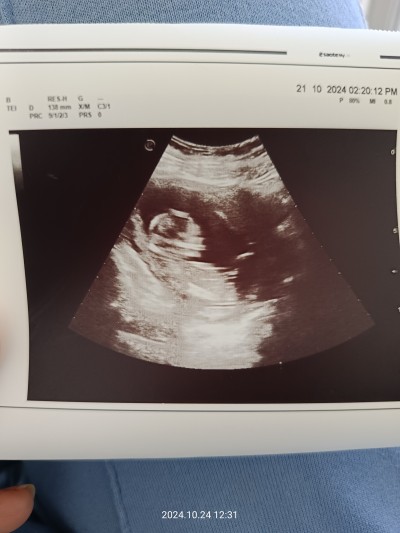

Cinsiyet tahminî yapabilir misiniz rica etsem?

13+6

Ultrason hic net degil canim sadece kafası net

Erkek hisetim ben